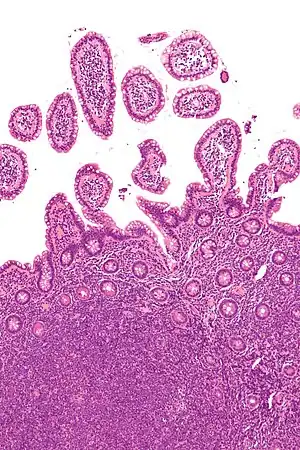

![]() | |

| Micrograph of mantle cell lymphoma, a type of non-Hodgkin lymphoma. Terminal ileum. H&E stain. | |